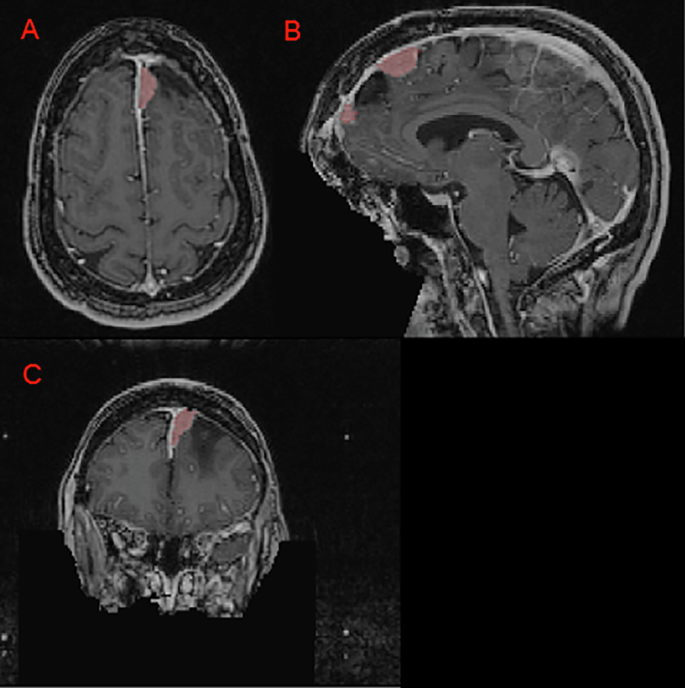

The imaging dataset includes exclusively 3D T1c brain MRI scans in native acquisition resolution in either the intact (Fig. 1) or postoperative setting (Fig. 2, 3), which mimics the data available for most radiotherapy planning. While additional sequences such as T1-weighted, T2-weighted, T2-FLAIR, and computed tomography are sometimes used in clinical workflows, these were not consistently available nor required for RT planning at all centers and were therefore not included in the dataset.

Panels A, B, and C depict a left anterior falcine meningioma (red) on axial, sagittal, and coronal images respectively. Panel B demonstrates an area of hypointense encephalomalacia between two separate anterior falcine meningioma components. Panels B and C highlight the defacing process, which removes pixels in and around the face to eliminate potentially identifying facial features.